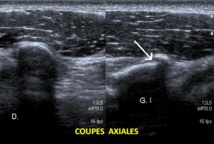

C'est en inspectant la région antérieure de l'épaule qu'a été constatée une interruption de la corticale osseuse sur le segment horizontal de la coracoïde.

Cette anomalie a été confirmé sur 2 coupes distinctes.

A noter que l'on n'observe pas d'hématome à proximité de l'interruption de la corticale osseuse, la lésion remontant à plusieurs semaines.